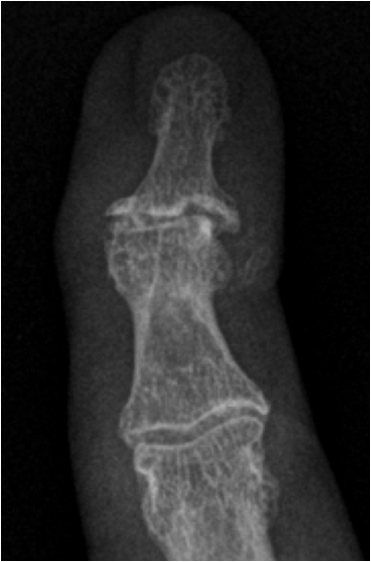

Fig. 11. Growth plate fracture with involvement of metaphysis and epiphyis (Salter-Harris type IV.